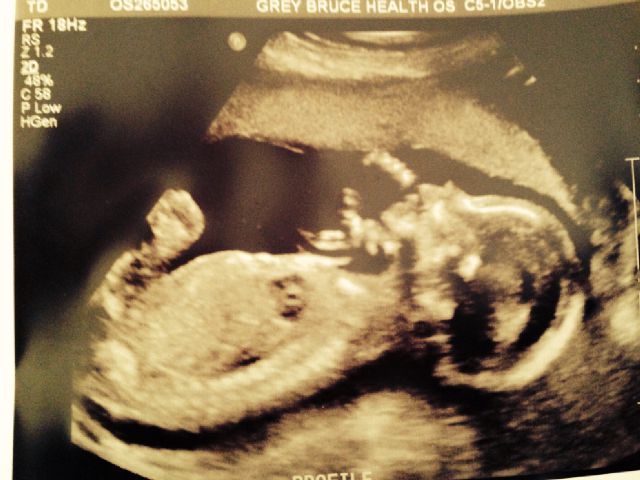

This is my story. My husband and I decided we wanted to do a gender reveal at our 20 week ultra sound. The tech had a student and seemed very distracted. The scan was very quick...and I looked very closely to see if I could spot gender. Since we had asked her to write the gender on paper so we could open it privately she didn't show us "the goods" at least to our knowledge. So she took a very clear potty shot doing femur measurements...very clear...both my husband and I saw NOTHING at all in between the legs...no protrusion at all. We have a boy and found out with our first and was shown a penis in between the legs. After the potty shot I asked "Just out of curiousity...do you know the gender...and she says "I THINK I know what it is." After the scan, she was just said "have a nice day, and forgot my husband and I wanted to know the gender...we had to remind her. SO she writes down on a piece of paper and my husband and I go out to the car to read "BOY". We were kind of surprised but are excited and have been buying blue and decorating for a boy. Fast forward to 26 weeks later...I decided to ask the OB Dr I saw to review my scan to confirm the gender...and after some long sorting through pics...he says "There is no scrotum visible or boy parts, so 50,50. I am so confused now...I know he must of saw the same shots my husband and I saw at the live scan which showed nothing between the legs. How certain would you all be after this experience. I should say my scan was at 19 weeks and 1 day..but baby was almost measuring 21 weeks. Please help!!!

I am starting to wonder....can you ever tell gender from a femur shot?!?!?!?!